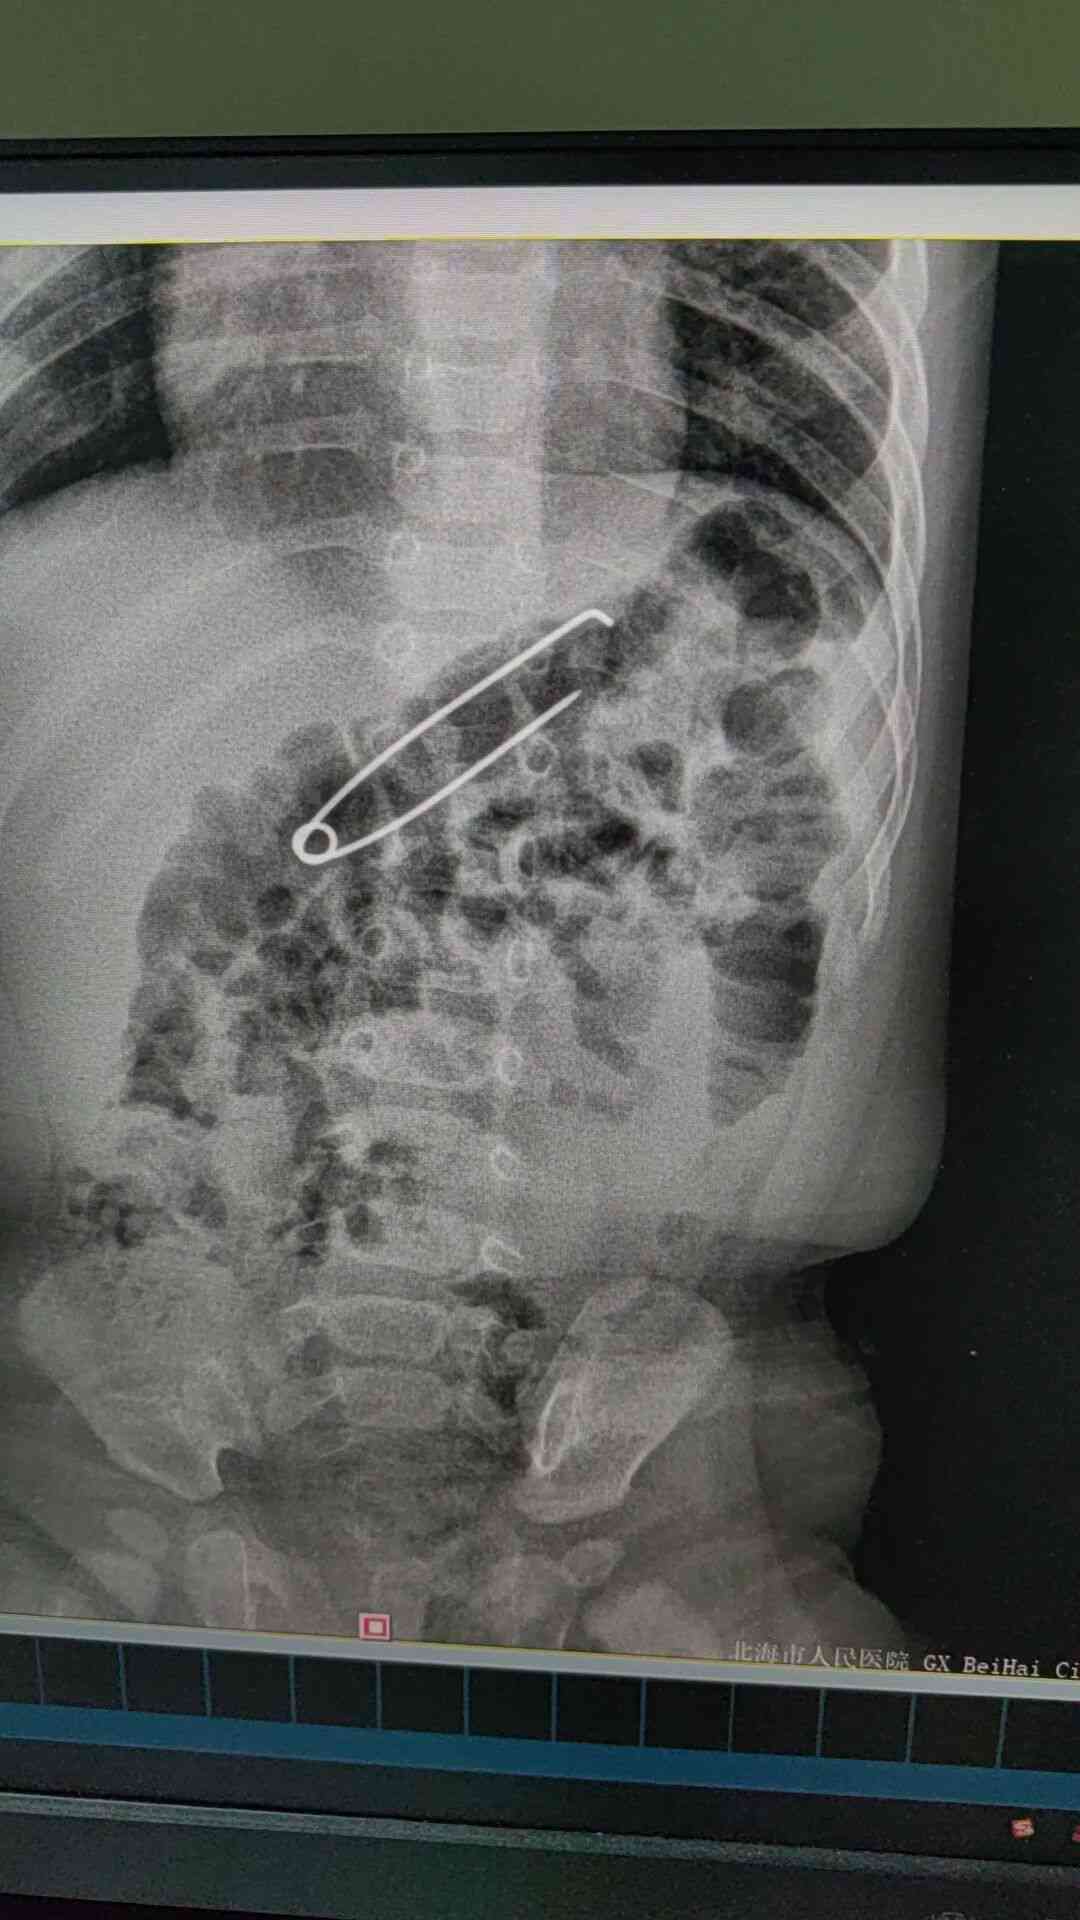

患儿家长发现宝宝误吞扣针后,紧急送至市人民医院银滩院区急诊科。接诊医生立即完善拍片检查,确认异物存在后,迅速组织消化内科、小儿外科等多学科会诊。考虑患儿月龄小、扣针体积较大,为最大限度保障手术安全与术后复苏效果,医院第一时间将患儿收入儿科住院治疗。

患儿收入儿科病房后,值班医师包少萍副主任医师和主治医师伍际玉等医护人员立即为其完善CT检查,明确扣针位于胃内,同时联系消化内科、麻醉科和手术室做好急诊手术准备。4日晚,消化内科副主任谭丽团队在手术室气管插管全麻下,通过胃镜微创操作,精准将胃内扣针顺利取出。取出的扣针长5厘米宽1.2厘米。“幸好扣针是扣着的,如果针尖打开,后果不堪设想。”谭丽医生说。